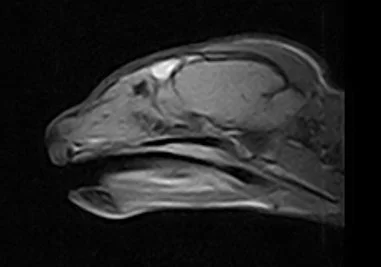

Physical exam was unremarkable except for a bilateral green purulent nasal discharge and episodic sneezing.  MRI

(shown left) revealed diffuse soft tissue density bilaterally in the rostral nasal cavity without turbinate destruction.  Rhinoscopy revealed a normal posterior nasopharynx, with soft tissue swelling and purulent discharge in both nasal passages.  Histopathology of biopsy samples obtained from the nasal mucosa revealed bilateral chronic lymphoplasmacytic follicular rhinitis, with focal areas of neutrophillic infiltrates.  Culture of the nasal mucosa biopsy specimens yielded Pseudomonas.